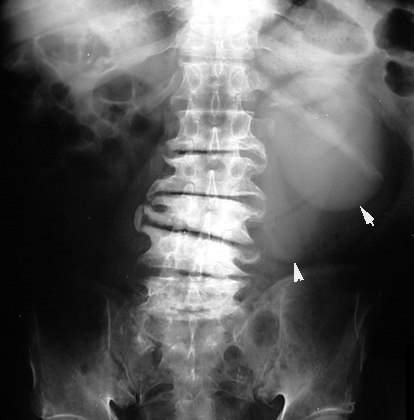

Spine x-ray shows severe osteoarthritic changes of lower lumbar spine. Incidentally there is a soft tissue mass overlying left renal area. Workup of this incidental mass turned out to be Simple Renal cyst.

Renal Masses are often detected as an incidental finding on KUB or IVP.  Ultrasound would be the first test of choice to characterize the mass since no IV contrast or radiation is used. It is ideal for children, pregnant women and patients with renal failure. If the lesion is clearly cystic, no further test is necessary. If solid, contrast CT should be done.